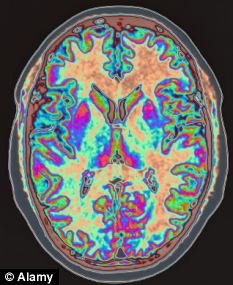

科学家通过功能成像学的研究,发现在人的大脑结构中扁桃形结构颞叶过度的活跃是造成创伤后应激障碍(PTSD)的主要原因,在恐惧、焦虑和害怕中扮演着一个关键的角色。